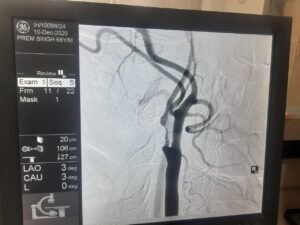

एक साल पहले प्रेम सिंह को स्ट्रोक हुआ था, जिससे उनके शरीर के बाएं हिस्से में कमजोरी आ गई थी। हालिया जांच में पता चला कि उनकी दाहिनी कैरोटिड आर्टरी में 95-99% तक गंभीर रुकावट थी, जो भविष्य में फिर से स्ट्रोक का बड़ा कारण बन सकती थी।

डॉक्टरों की मल्टीडिसिप्लिनरी टीम ने स्टेंट लगाने के बजाय सर्जरी को अधिक सुरक्षित विकल्प माना, क्योंकि रक्त नली में मौजूद प्लाक बहुत नरम और नाजुक था, जो टूटकर मस्तिष्क तक पहुंच सकता था। इसलिए Carotid Endarterectomy की सिफारिश की गई, जिसमें गर्दन की धमनी को खोलकर जमा प्लाक को सावधानी से निकाला जाता है।

सर्जरी डॉ. रोहित चौहान (सर्जन, जीबी पंत अस्पताल दिल्ली से प्रशिक्षित) द्वारा की गई। ऑपरेशन के दौरान Pruitt–Inahara Shunt जैसे विशेष उपकरण का उपयोग किया गया, जिससे सर्जरी के दौरान मस्तिष्क में रक्त प्रवाह निरंतर बना रहा और स्ट्रोक का खतरा न्यूनतम रहा। सर्जरी में बड़े, नरम और वसा युक्त प्लाक के टुकड़े निकाले गए, जिससे टीम का निर्णय पूरी तरह सही साबित हुआ।